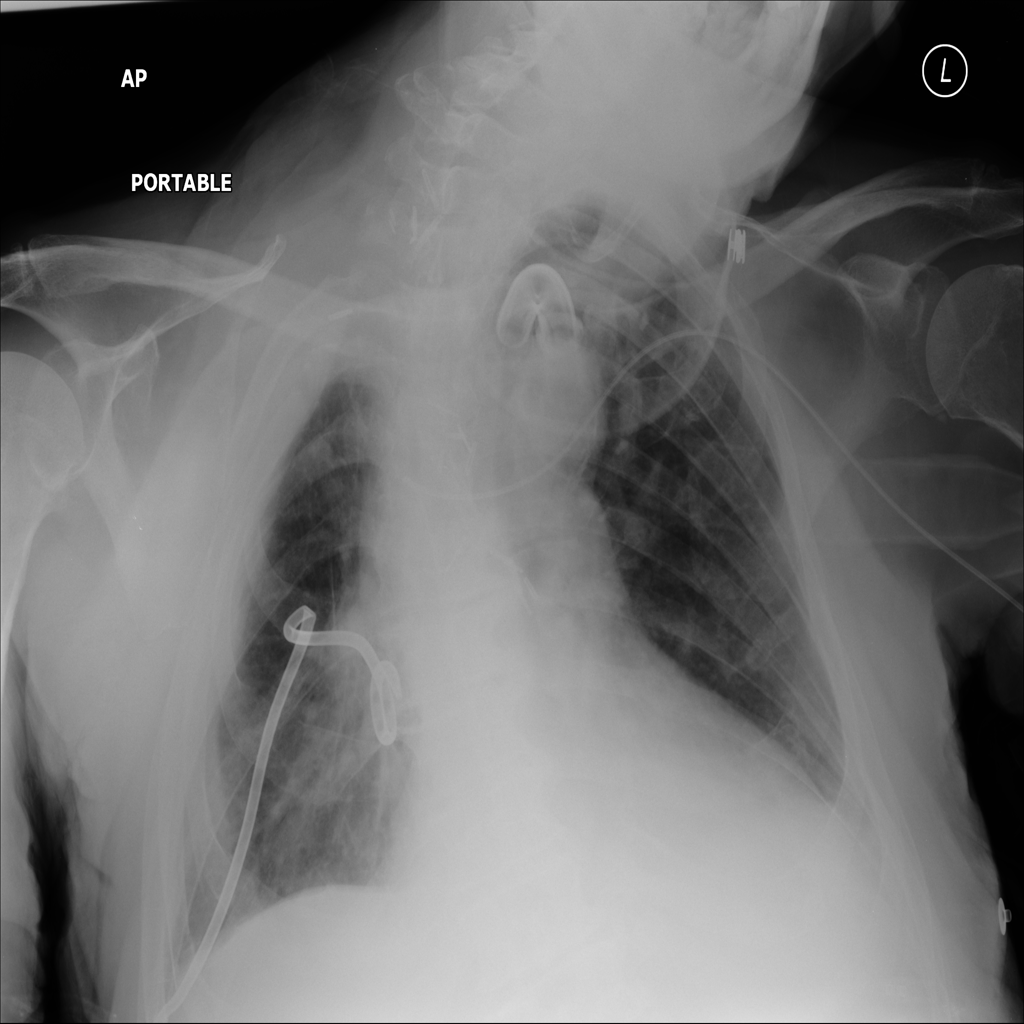

Mass

A mass is a larger focal opacity or lesion seen on the image. It is a descriptive finding that can have several causes and usually needs more imaging or clinical context to characterize.

PAT-E1D6 · IMG-006Mass

PAT-E1D6 · IMG-006

AP